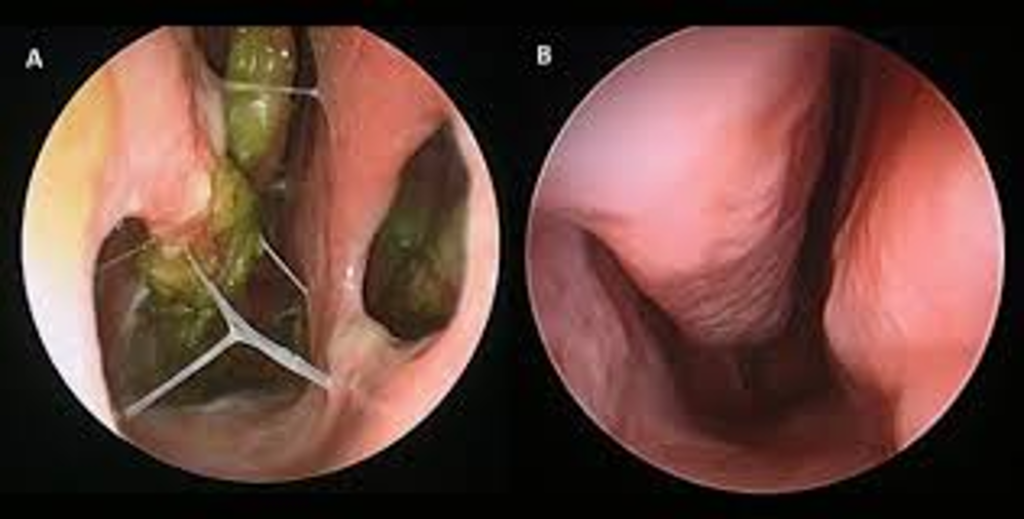

A physical examination of the nasal cavity allows the doctor to assess the condition of the turbinates and other nasal structures. During this examination, the doctor can evaluate whether the turbinates have been excessively removed, the condition of the nasal mucosa, and the width of the nasal airways. This examination can be enhanced with an endoscopic procedure, allowing detailed visualization of the nasal cavity and detection of abnormalities in the nasal tissues.

Imaging Techniques:

In some cases, the doctor may order a CT scan (computed tomography) or MRI (magnetic resonance imaging) to better assess the structure of the nose and sinuses. These imaging techniques can provide detailed views of the structural changes in the nose and the condition of the turbinates. These tests can also help differentiate ENS from other causes of nasal obstruction.